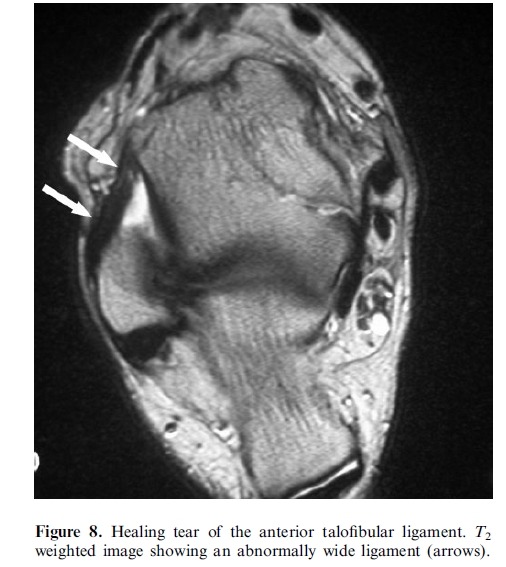

Imaging plays a major role in the management of ankle and foot problems. Most conditions are assessed by plain

films alone. MRI is an excellent technique for those cases where the diagnosis is uncertain as it can exclude most

clinically relevant pathologies. Ultrasound is an excellent tool for imaging focal soft tissue abnormalities. CT is

occasionally useful when bony detail is required. Bone scintigraphy has a limited role and has been largely replaced by MRI in many centres. The main reasons for referral are swelling and pain. Many conditions of the ankle and foot are related acute or repetitive trauma.

# MRI is the most suitable technique for global assessment of bone and soft tissues for persistent pain following injury.